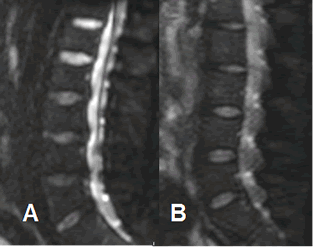

Fig 223. Fracturas por osteoporosis.

A: RM sagital en T1, B: RM sagital en STIR y C: RM sagital en difusión.

Pérdida de altura en varios cuerpos vertebrales dorsolumbares. En T1 conservan su señal y sus bordes son angulados, lo que sugiere etiología benigna. (Flechas delgadas). La vértebra D11 es algo hiperintensa en la parte anterior, indicando evolución aguda. (Flecha gruesa). Todos los cuerpos son hipointensos en la difusión, por fracturas de origen osteoporótico.